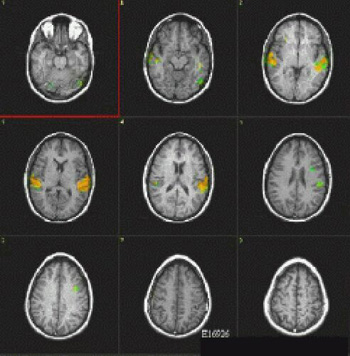

La imagen de resonancia magnética funcional tiene una terminologia particular. Las siguientes imágenes explican los términos más importantes que se usan para describir un experimento.

Un nivel es la localización del sitio a explorar. Se pueden explorar varios niveles al mismo tiempo.

En este gráfico se muestran: 5 períodos ON, durante el cual el sujeto realiza la tarea; 5 períodos OFF, durante el cual el sujeto descansa; cada período tiene 30 segundos de duración por una cantidad total de 5 minutos de duración del experimento. Se exploran cuatro niveles del cerebro, con 120 imágenes (o escanes) divididos alternamente en grupos de 12.

Un resultado final

Las áreas a color muestran la activación de las regiones del cerebro involucradas en oír y entender la voz humana. El hemisferio izquierdo muestra una activación mayor.